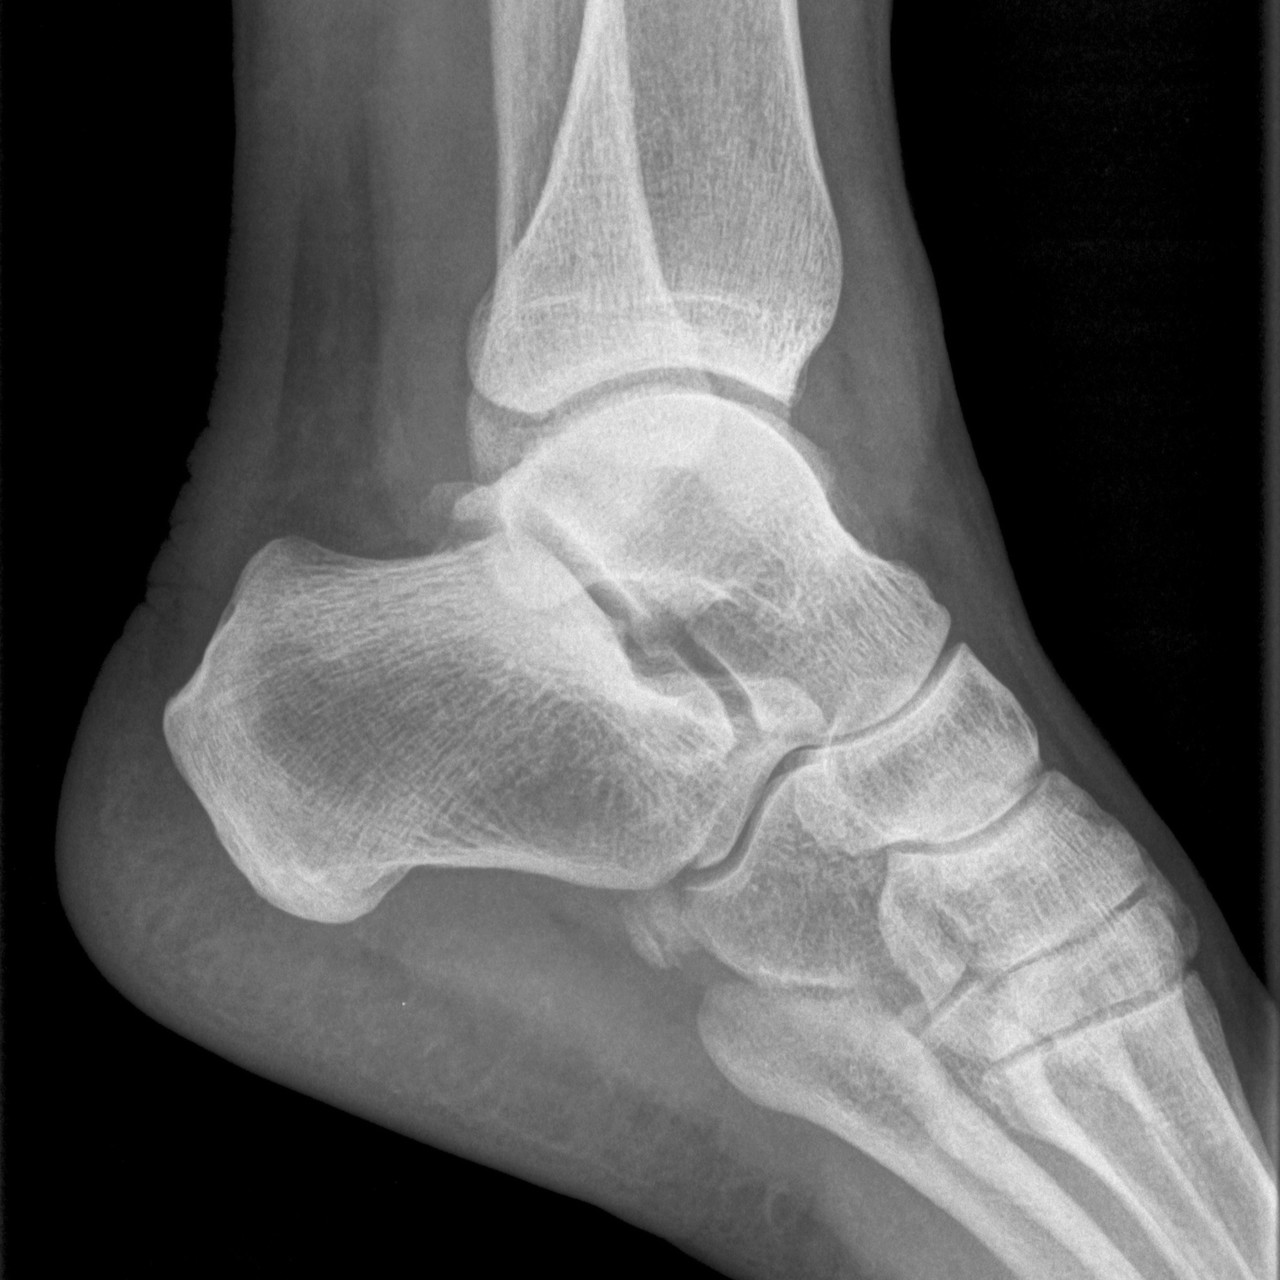

영상의학 검사

방사선 검사를 통해 해부학적 이상 소견 및 발의 정렬, 아치의 높이등을 확인하고 정밀 초음파로 인대 손상여부와 정도를 정확하게 파악하여야 올바른 치료의 방향을 결정할 수 있습니다.

영상의학검사

무지외반증은 대부분 엑스레이 등으로 간단하게 진단이 가능합니다. 발 변형이 있다면 전문의와 상담을 통해 현재 상태를 확인하고 보정해 줄 수 있는 신발이나 깔창을 선택해 신는 것이 좋습니다.

무지외반증은 대부분 엑스레이 등으로 간단하게 진단이 가능합니다.